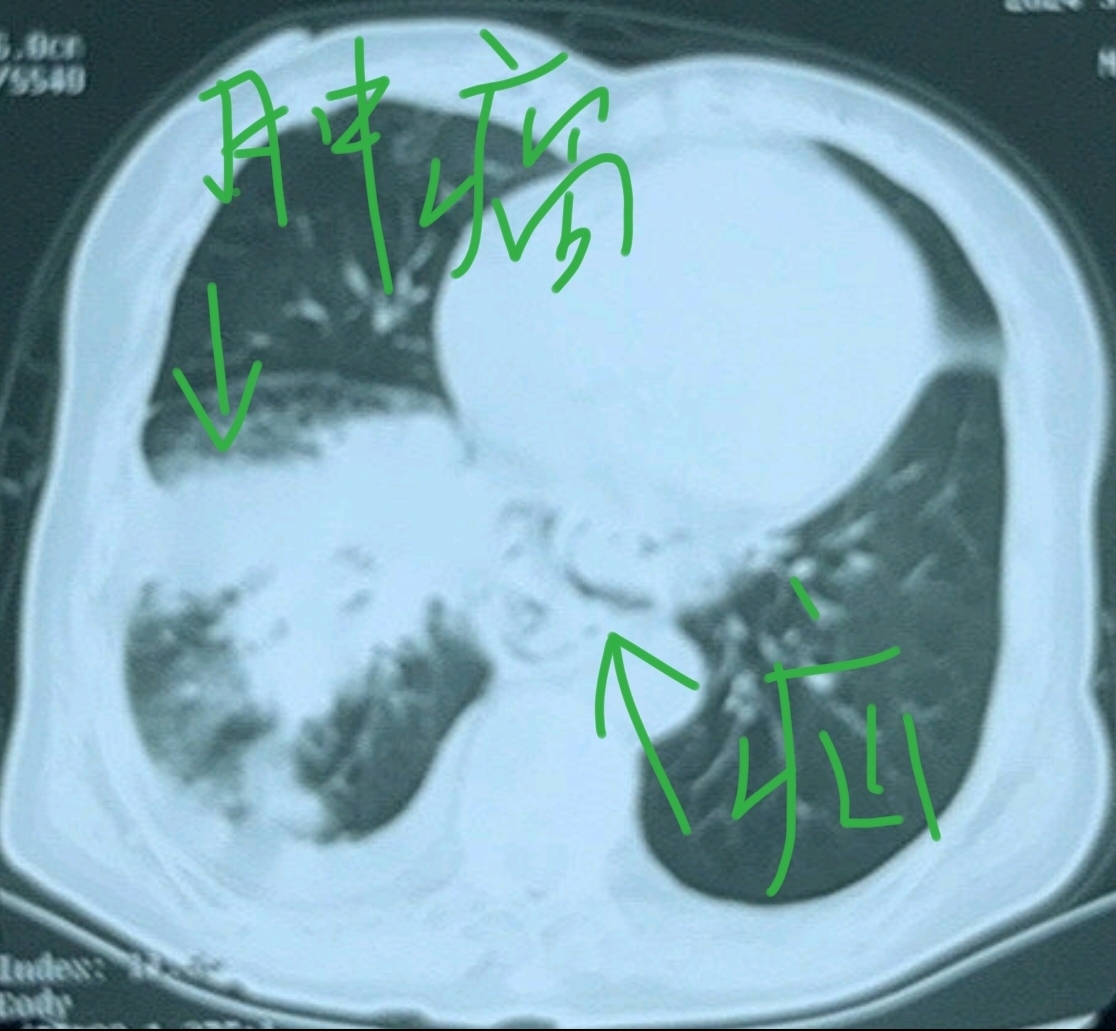

肺部CT能检查出肺癌吗

CT可以查出部分肺癌,但不能确诊所有肺癌,需结合其他检查方法CT检查通过扫描肺部,可发现结节肿块或其他异常阴影,帮助医生判断是否存在肿瘤对于较大的肿瘤或伴有纵隔淋巴结转移的肺癌,CT的诊断准确性较高,能够清晰显示病变...